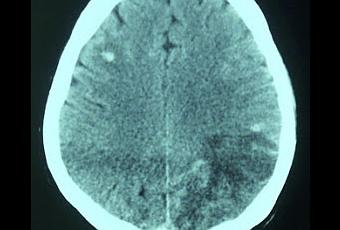

Tomodensitométrie en coupe horizontale avec injection de produit de contraste, montrant un double foyer d'accident vasculaire cérébral (AVC) ischémique pariéto-occipital gauche et frontal droit avec ramollissement hémorragique. In Annales Françaises d'Anesthésie et de Réanimation Volume 31, Issue 1, January 2012, Pages 82-85

Source iconographique et légendaire: http://www.sciencedirect.com/science/article/pii/S0750765811004096